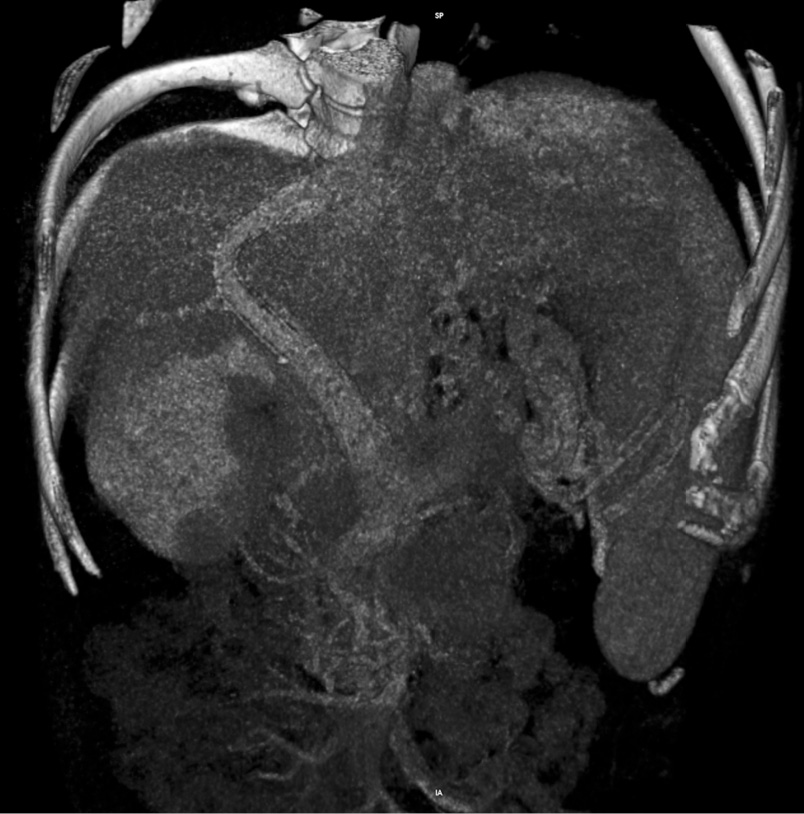

Пациентка наблюдается в течение 12 лет. При регулярных контрольных обследованиях признаков рецидива онкологического заболевания не выявлено. В 2017 г. пациентка прошла полный курс безинтерфероновой терапии противовирусными препаратами прямого действия по поводу хронического вирусного гепатита С. На фоне элиминации вируса отмечена положительная динамика в функциональных показателях печени. У пациентки на настоящий момент печеночная недостаточность класса А (Child-Pugh). При выполнении контрольной КТ-ангиографии TIPS проходим (рис. 4 А, Б). Асцита нет. Варикозное расширение вен пищевода 1-й ст. Прогрессирования печеночной энцефалопатии не отмечено. Пациентка профилактически получает препараты лактулозы и орнитина.